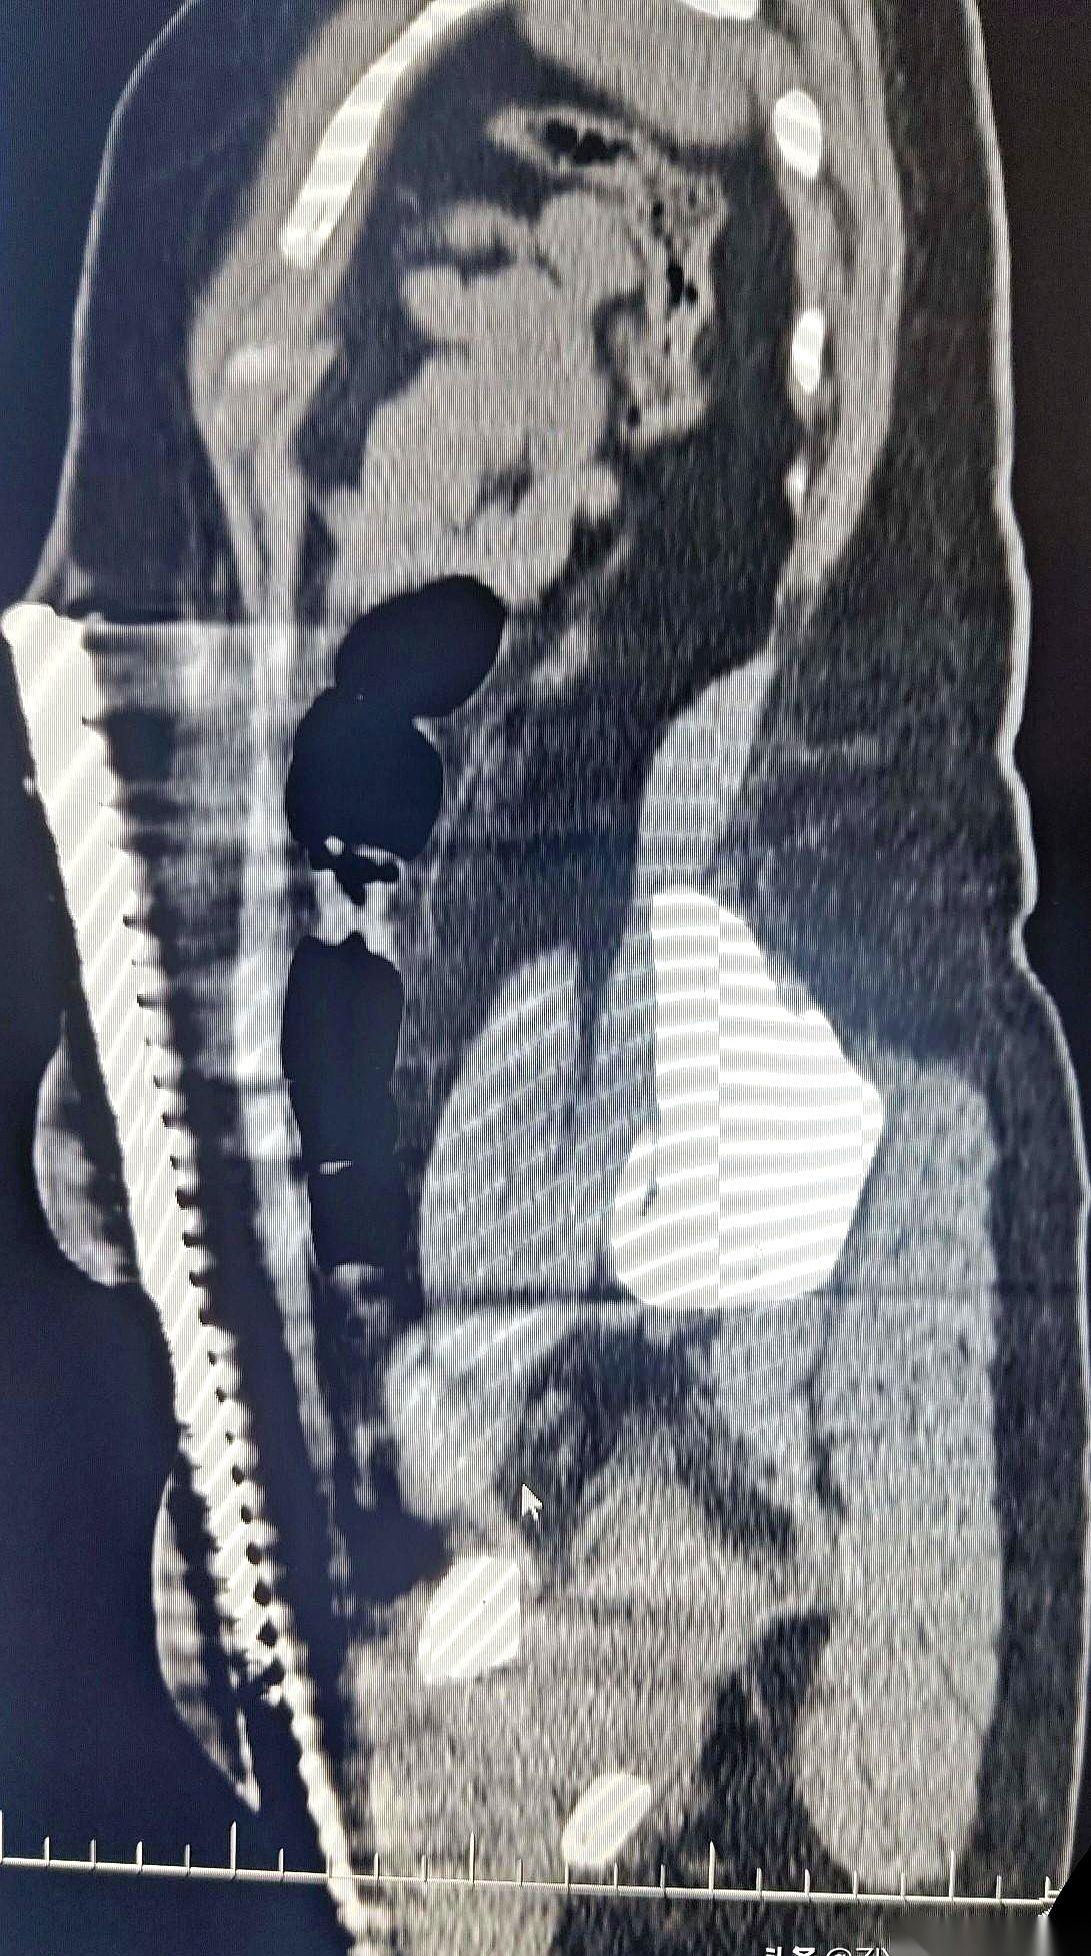

急诊室的门一推开,所有人的声音都小了下去。 担架上躺着一个女人,47岁,工地上干活的。一根粗钢筋,从她身体下方贯穿,从另一头的腹部皮肤顶了出来。人是清醒的,但脸上没有一丝血色,嘴唇抖得说不出话。 没人敢碰那根钢筋。谁都清楚,这玩意只要偏一毫米,里面就是肠子、大血管。现在拔,等于亲手送她走。 检查室里,气氛凝重得像块铁。医生们盯着CT机,等着那个最终的“判决书”。机器嗡嗡作响,屏幕上,一帧一帧的黑白影像缓缓生成。 所有人都凑了过去,死死盯着那条刺眼的金属白线。 它进去了。斜着向上。然后,就在快要碰到一堆要命的器官时,它拐了个弯,贴着内壁,硬生生从脂肪层里挤出了一条路,最后从肚皮下钻了出来。 就差那么一点点。 一名老医生摘下眼镜,反复擦了擦,又戴上,再看一遍。没错,钢筋完美地避开了所有脏器。那个救了她命的东西,是她厚厚的脂肪。 这层平时可能让她烦恼的脂肪,像个垫子,硬是把死神的刀给隔开了。 只能说,有时候,你身上最嫌弃的东西,恰恰是你的保命符。